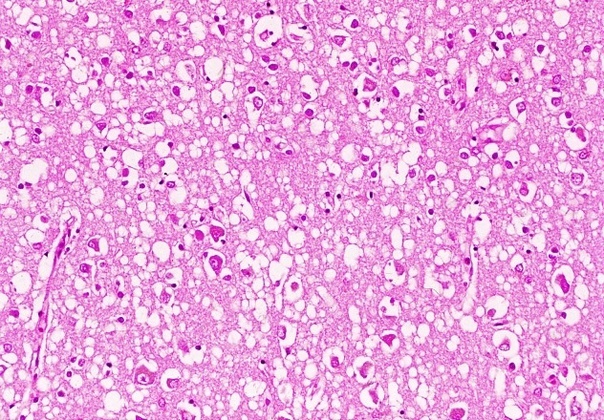

В противоположность этому инфекционный белок PrPSc накапливается в цитоплазменных везикулах, что приводит к последующему нарушению функции синапсов и развитию глубоких неврологических дефектов. Позднее PrPSc высвобождается во внеклеточное пространство и откладывается в виде амилоидных бляшек. PrPSc форма обнаружена в организме людей и животных, больных прионными заболеваниями – трансмиссивными спонгиоформными (губкообразными) энцефалопатиями.

Поскольку этиологическим фактором развития спонгиозных энцефалопатий служит белок, исследователи столкнулись с единообразием патологических изменений ЦНС, что, в сущности, и послужило поводом для объёдинения этих заболеваний в единую группу.

При болезни куру патологические изменения можно наблюдать только в центральной нервной системе. Обычно они выражаются в формировании типичной губчатой энцефалопатии. В коре, подкорковых ядрах, подбугорной области и в мозжечке наблюдается вакуолизация дендритов, аксонов и тел нейронов. Вакуолизация становится настолько выраженной, что серое вещество коры большого

Изменения нейронов сочетаются с гипертрофией и размножением астроцитов. При куру у человека патогистологические изменения наиболее выражены в мозжечке: появляются аморфные ШИК-положительные бляшки, содержащие амилоид, уменьшается количество грушевидных нейронов (клеток Пуркинье). Вместе с тем, при куру не удаётся обнаружить воспалительной реакции, столь характерной для многих заболеваний ЦНС, или таких характерных признаков вирусной инфекции, как образование телец включений или глиальных узлов.

Таким образом, морфологически прионные болезни можно отнести к группе амилоидозов. Амилоидоз при прионных болезнях характеризуется отложением волокнистого амилоидного белка в головном

Тем не менее, при большом сходстве патогистологических изменений между болезнями Крейтцфельдта-Якоба, куру и скрепи имеются отличия. Так, амилоидные бляшки при болезни Кройцфельдта-Якоба наблюдаются в 9%, а при куру они встречаются в 70% случаев.